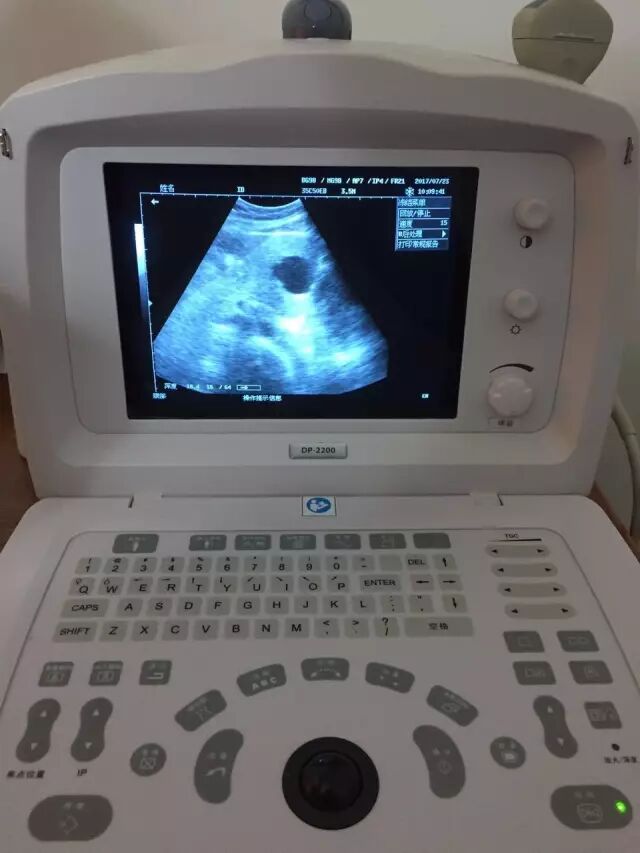

↑图:B超检查

↑图:先进的便携式B超仪,可清晰检查出是否有病患